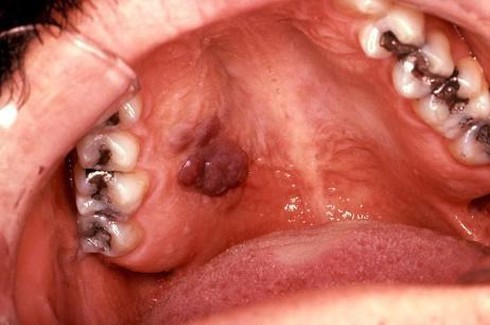

![]() |

Giang mai là chứng bệnh đặc biệt nghiêm trọng với tình dục miệng. Theo thống kê của các nhà khoa học Hoa Kỳ, có đến 15% số bạn trẻ nước này mắc phải giang mai qua quan hệ miệng